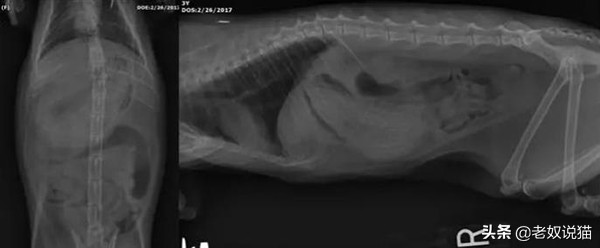

二、误食发圈的猫

美国一只叫Winnie的猫误食46根发圈